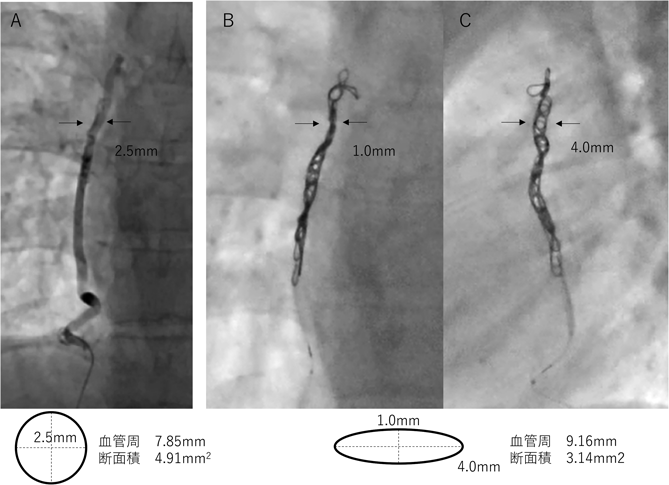

c.柔らかい血管

静脈静脈短絡では動脈に比べ柔らかく,また小児では動脈でも成人と比べると柔らかく,大きめのコイル径が選択されることが多い.親カテが安定していれば当院では血管径の3~4倍の二次コイル径のものを選択して効率的な塞栓を行っている.Fig. 4Aの症例では,正面像2.5 mm×側面像2.5 mmの静脈静脈短絡血管に対してTarget™ XXL 6 mm×40 cmを八の字型に留置したところ,1本で塞栓された.留置後のコイル形態をFig. 4B, Cで見ると矢印部分でのコイル径は正面像1.0 mm×側面像4.0 mmであり,大きいコイルを使用することで血管が楕円状に変形したことが確認された.これを血管の断面で考えるともともとの血管の血管周長=7.85 mm,断面積=4.91 mm2に対して,コイル留置後の楕円の血管周長=9.16 mmと伸長したが断面積は3.14 mm2と減少していた.柔らかい血管では大きめのコイルで血管を楕円状にしたほうが血管の断面積を減らすことができ効果的な塞栓が期待できると我々は考えている.

Fig. 4 柔らかい血管に対する効果的なコイル塞栓

19歳フォンタン患者の静脈静脈短絡.A: 留置前正面像,B: 留置後正面像,C: 側面像.2.5 mm径に対してTarget™ XXL 6 mm×40 cmを八の字型に留置したところ血管が楕円状に変形していた(計測値は矢印部分の血管,コイル径).変形後の楕円の血管周長はコイルにより伸長していたが断面積は減少しており,楕円状にすることで塞栓効果を高めることが期待できる.